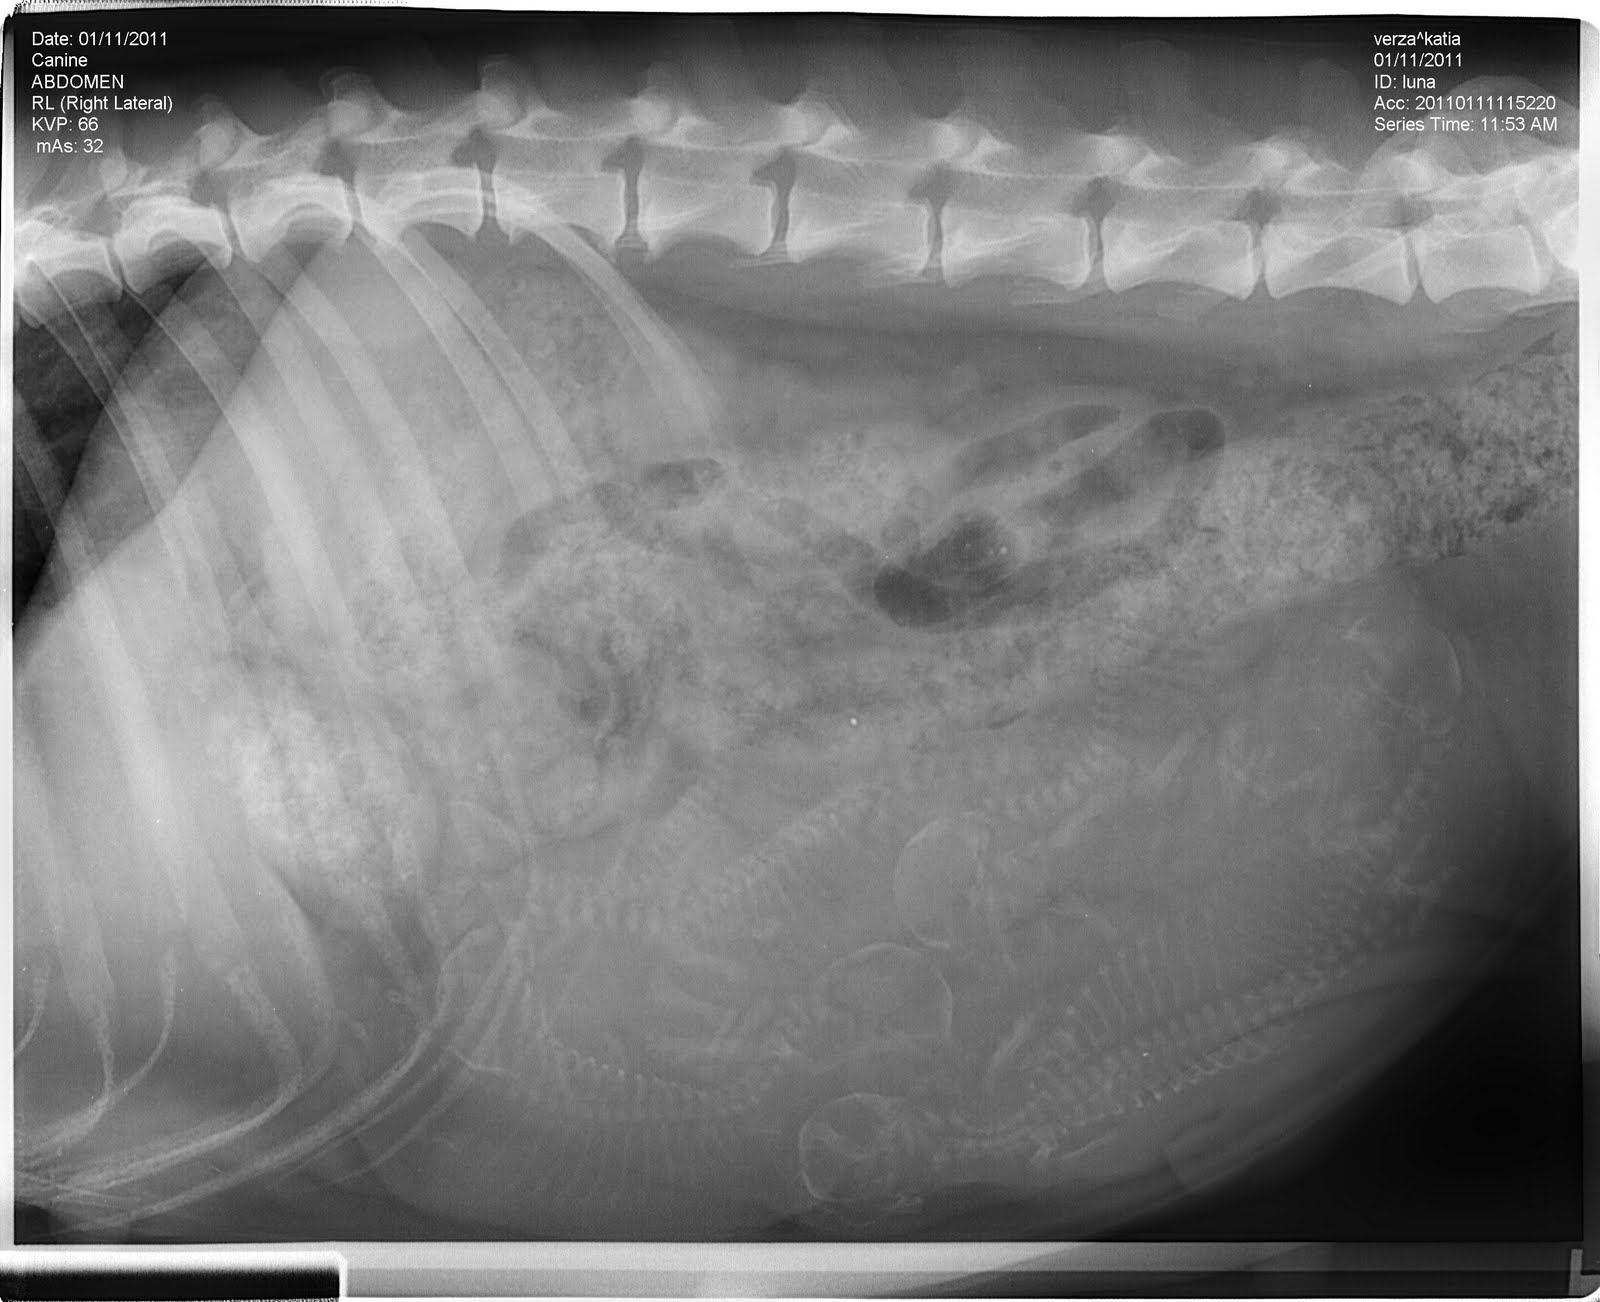

As I promised, there X-rays taken place on 11 January.

They number between 6 and 7, but unfortunately the Moon was full of feces and abdomen and then the count is a little uncertain ...